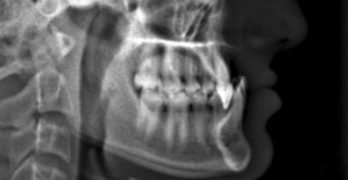

Para comenzar la semana traemos un artículo llamado Asymmetric mandibular arch distalization with third-molar … [Leer más...] acerca de Distalización asimétrica con extracción de terceros molares para la corrección no quirúrgica de la mordida abierta esqueletal clase III y desviación mandibular

Distalización asimétrica con extracción de terceros molares para la corrección no quirúrgica de la mordida abierta esqueletal clase III y desviación mandibular